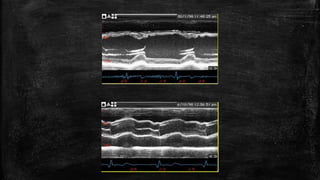

B- Brightness

mode shows

the energy as

the brightness

of the point

M- Motion mode the

reflector is moving so

if the depth is shown

in a time plot, the

motion will be seen

as a curve